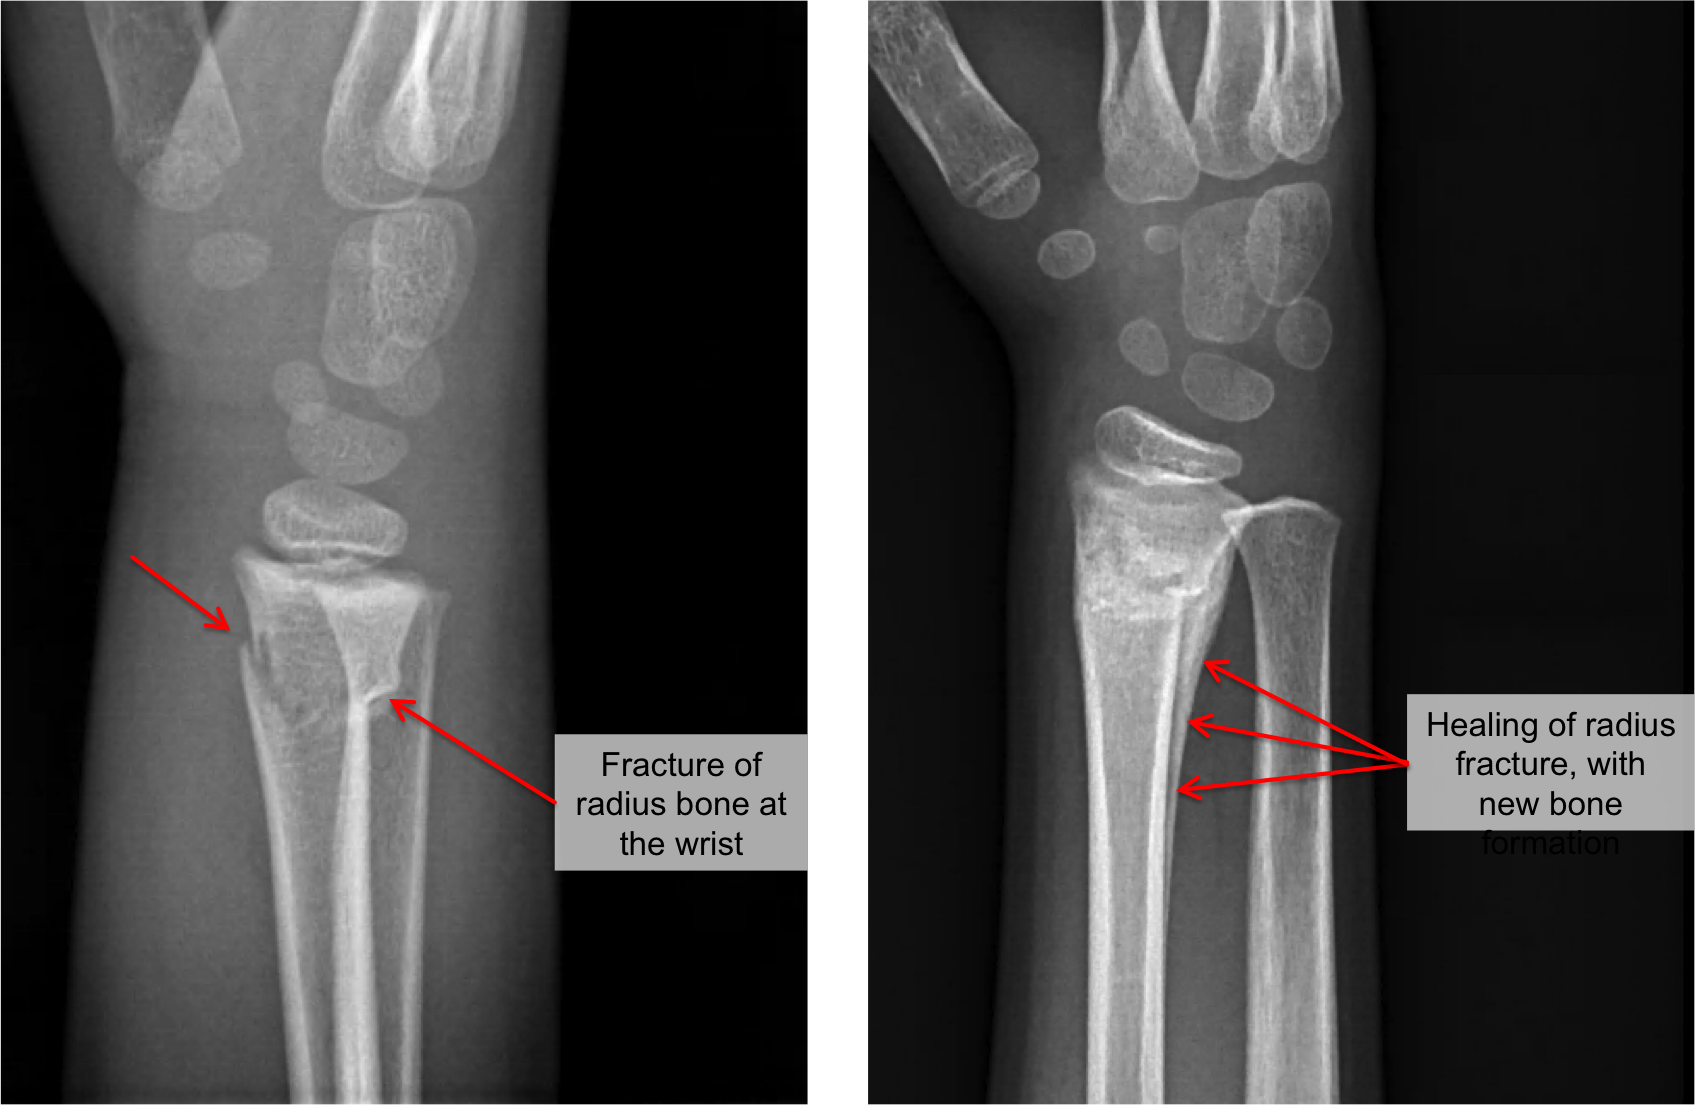

Distal Radius Fracture

Distal Radius Fractures SimcoeMuskoka Orthopaedics

What Is a Distal Radius Fracture? Youssra Marjoua, M.D. Baltimore, MD

Distal Radius Fracture Raleigh Hand Surgery — Joseph J. Schreiber, MD